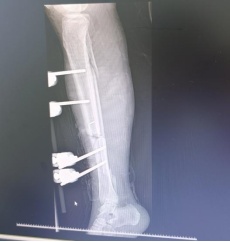

最后一步,就是固定骨骼,重建下肢力线。针对多项粉碎性骨折、骨缺损情况,手术团队采用外固定支架临时复位固定,既保证肢体形态,又为二期缺损的骨修复预留空间。

“手术中,患者输血量高达2400毫升,相当于半个成年人的全身血量。”佛山市康复医院(佛山市第五人民医院)骨科住院医师任庭杰介绍,这是一场艰难的保肢战,但整个团队配合极其默契、高效,不到3小时就赢得了手术的成功。